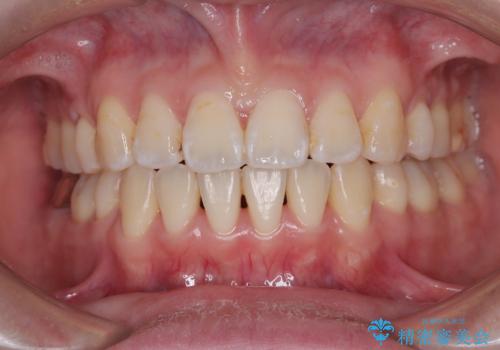

- 抜歯をせず前歯の角度を改善するマウスピース矯正治療

- 奥歯の咬み合わせのズレと前歯の突出感 変則的な抜歯矯正

- 【抜歯】ハーフリンガル矯正で韓国美人な横顔へ!

- 前歯を後ろに下げたい ワイヤー矯正(クリア装置)